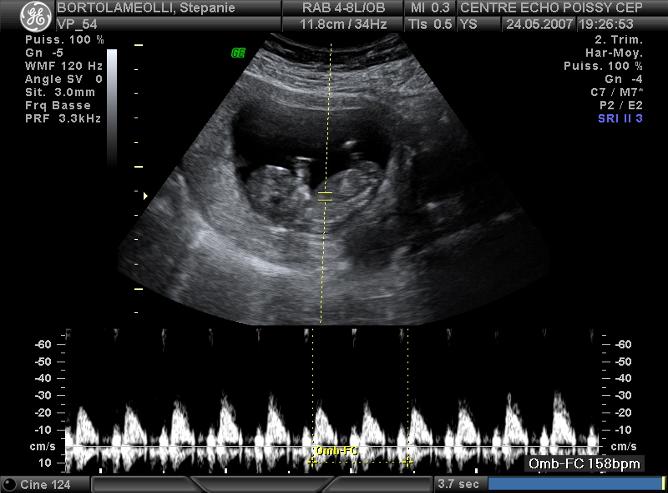

Echographies